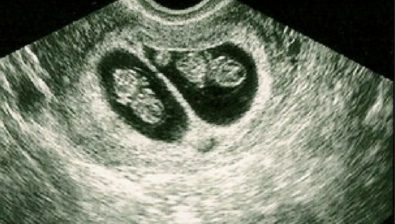

Ultrasound at 7 Weeks

Along with the tiny little arm and leg buds protruding, your baby is also developing the cerebral hemispheres of the brain. Eyes and nostrils are growing, as well.

Although you baby’s intestines are maturing, they are heavily connected to the umbilical cord. Later, the intestines will descend into proper placement in your baby’s abdomen.

As well as the intestines, the appendix is present and the insulin-producing organ, the pancreas, is also maturing.

While still looking slightly tadpole-ish, your baby has a clearly defined heart bulging from the chest.

All of these wonderful developments won’t be visible on an ultrasound, but be confident that the little bean on the screen is growing by leaps and bounds!